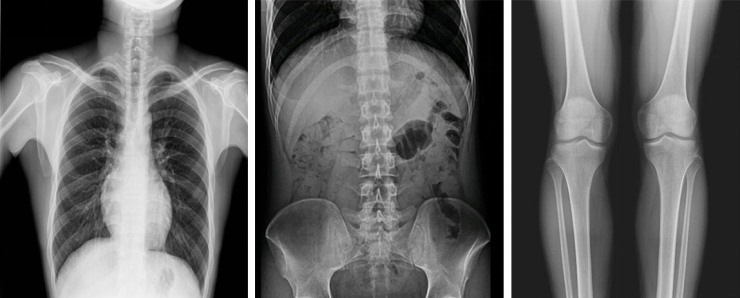

不同于常規(guī)靜態(tài)DR只能進行平片攝影檢查,動態(tài)DR可以滿足多種臨床檢查需求,包括靜態(tài)檢查、透視檢查、造影檢查、脊柱及下肢全長拼接檢查,相較于靜態(tài)DR具有豐富的臨床應用,且動態(tài)DR檢查更精準、直觀,擺位攝片效率極大地提升,大大節(jié)省拍片時間。

更多高級智能應用

動態(tài)DR影像采集幅面大,17×17英寸超大視野,可覆蓋成年人的全胸全腹,并且能在連續(xù)動態(tài)中實時高清點片,還可以進行視頻保存,在會診過程中可以回放影像檢查視頻,從而達到精準診斷的目的。同時動態(tài)DR還具有全身拼接功能,尤其適用于全脊柱和全下肢攝影,輔助脊柱畸形矯形治療、康復檢查,為臨床提供高精度圖像。